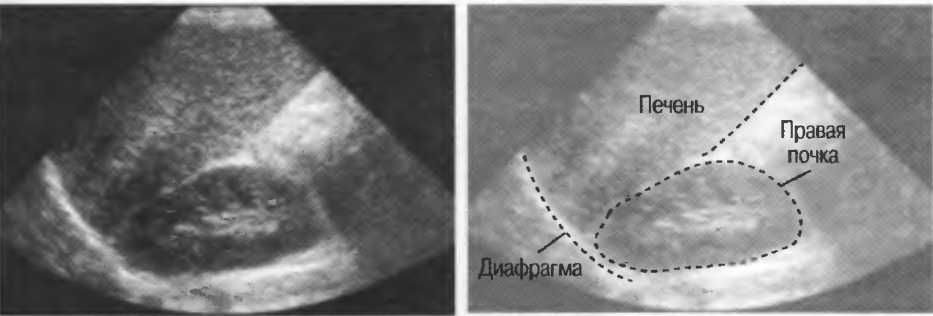

4. У здоровых обследуемых паренхима печени должна быть немного более эхогенна. чем кора рядом расположенной почки (рис. 26).

Рис.26. Продольный срез через печень и правую почку: нормальная паренхима печени более эхогенна, чем паренхима нормальной почки. Это еще один способ проверки качества изображения.